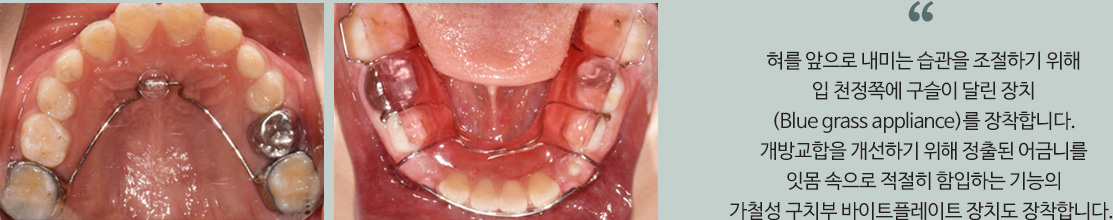

8세 아이로, 앞니 사이가 벌어지고 위아래 치아들이 맞물리지 못하는 개방교합입니다.

이 경우는 혀 내미는 습관에 의해 혀가 앞니를 앞으로 밀어서 발생한 것입니다.